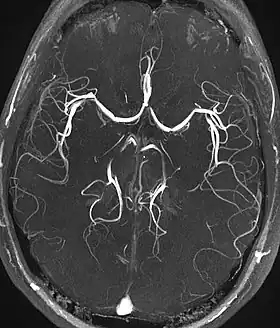

Magnetic resonance angiography (MRA) and venographyTime-of-flightTOFBlood entering the imaged area is not yet magnetically saturated, giving it a much higher signal when using short echo time and flow compensation. Detection of aneurysm, stenosis, or dissection[40]

Phase-contrast magnetic resonance imagingPC-MRATwo gradients with equal magnitude, but opposite direction, are used to encode a phase shift, which is proportional to the velocity of spins.[41] Detection of aneurysm, stenosis, or dissection (pictured).[40]